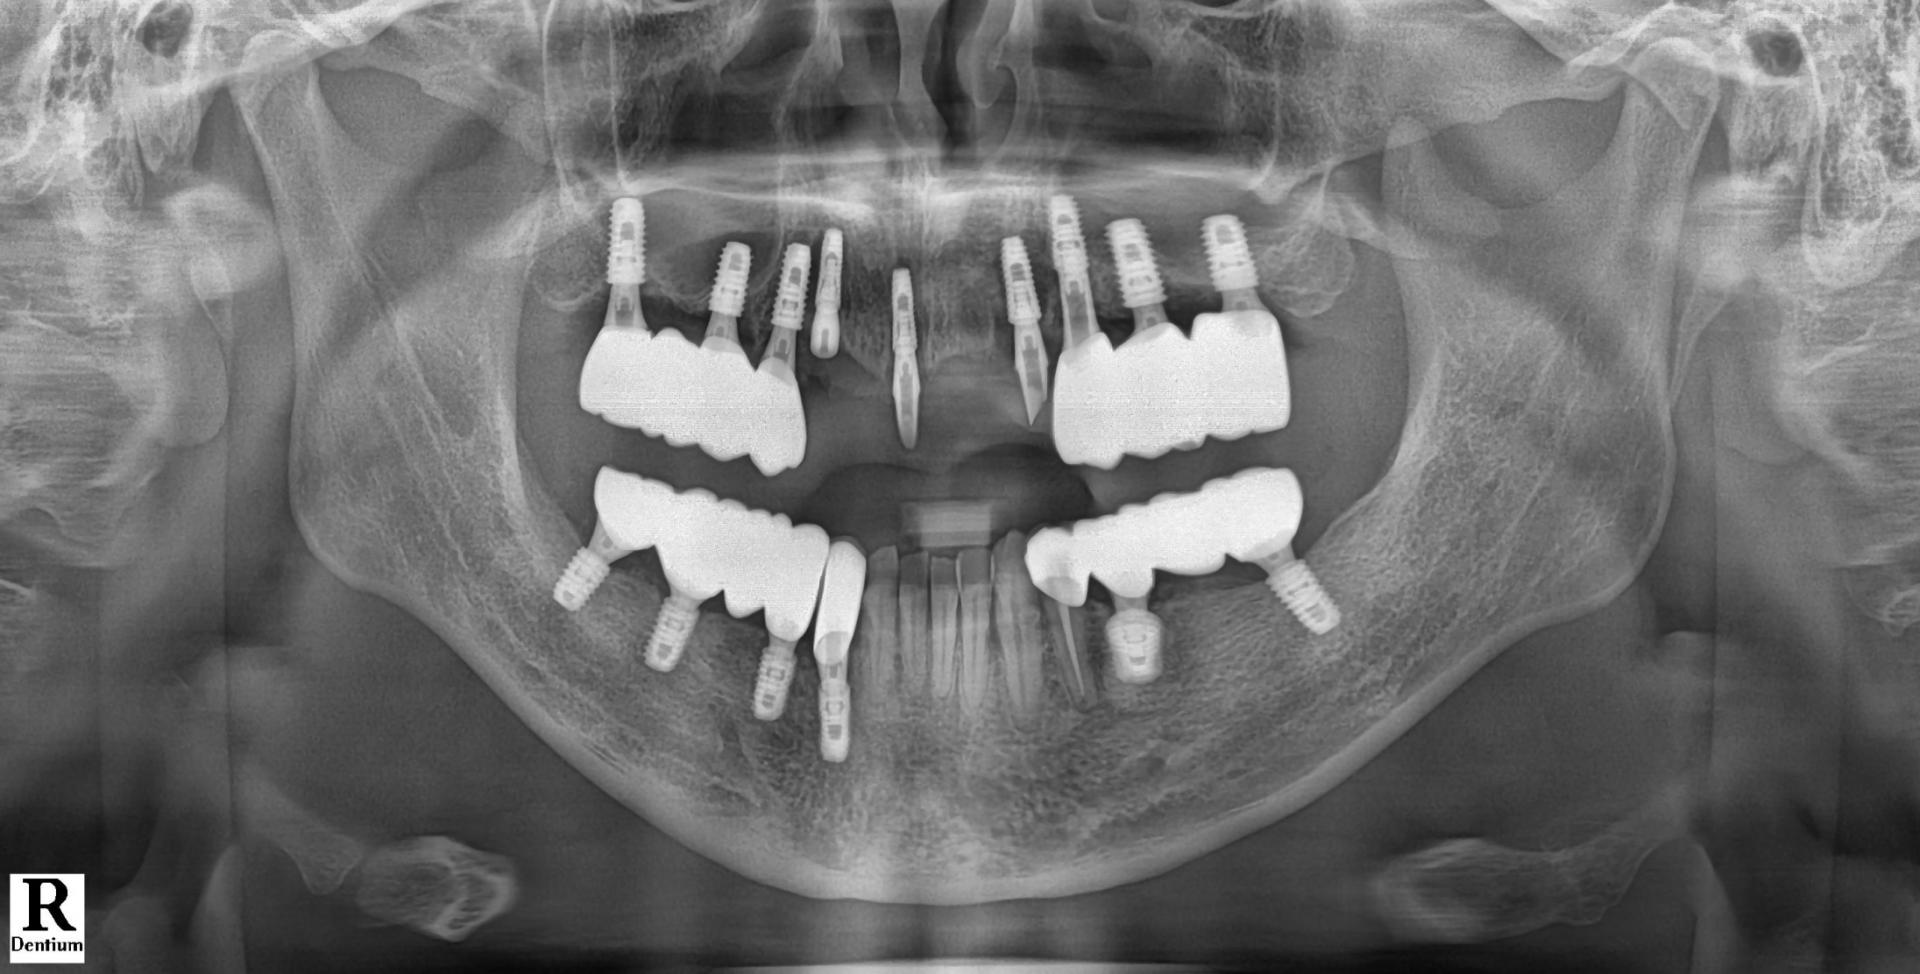

엑스레이 사진상에 위 앞니쪽 모든 치아뿌리 끝에 염증 병소가 보이고, 특히 우측 견치(송곳니)는 심한 우식으로 치관부(머리부분)가 전혀 남아있지 않은 상태였습니다.

해당 치아 3개 모두 발거하고 임플란트 수술 중간중간 방향을 확인하며 수술을 마무리 하였습니다.

치아 뿌리 끝 염증부위에는 모두 골이식을 동반하였으며, 수술 직후 바로 본을 떠서 다음날 아침 일찍 임시치아를 끼워드리기로 계획하였습니다.

임플란트는

덴티움社의 Superline 을 사용했으며 해당 부위 모두 적당한 위치로 식립되었습니다.

모든 임플란트에 연결하여 바로 임시치아를 만들어드리려고 하였으나 우측 송곳니 (사진상 좌측) 에는 치조골 상태가 좋지 않아서 다량의 골이식 및 임플란트를 잇몸 안에 묻어두기로 결정하였습니다.

따라서 가운데 임플란트와 좌측 송곳니 임플란트 (사진상 우측)만 기둥을 연결하여 임플란트 본을 떴습니다.